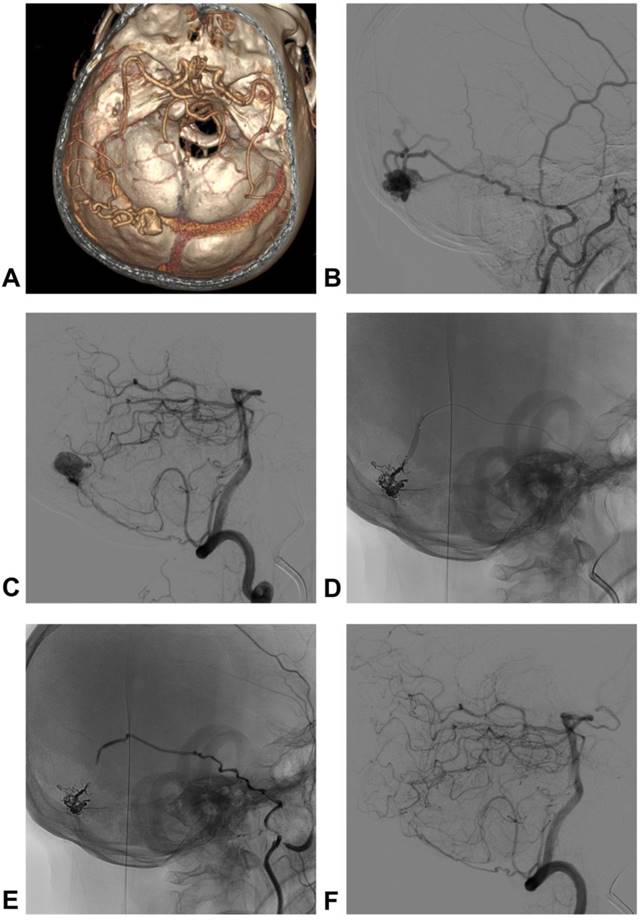

Four main meningeal arteries exist in the TSS region: the middle meningeal artery (MMA), ascending pharyngeal artery (APhA), posterior meningeal artery (PMA) and occipital artery (OA) [24, 25]. The posterior division (PD) of the MMA supplies the dura around the torcula, transverse sinus (TS) and sigmoid sinus (SS) [25]. The mastoid transosseous branch (MB) of the OA supplies the dura of the lateral and paramedial cerebellar fossa, including the TS and superior part of the SS [26]. The jugular and hypoglossal branches of the APhA supply the dura of the lower segment of the SS [27]. The PMA arises from the vertebral artery and supplies the dura forming the walls of TS and torcula [24]. The main meningeal vessels are shown in Figure 1.

Figure 1

Main meningeal vessel in TSS. A: The red region shows the PD of the MMA; the yellow region shows the PMA; B: the green region shows the MB of the OA; the blue region shows the APhA. Abbreviations TSS: transverse-sigmoid sinus; PD of the MMA: posterior division of the middle meningeal artery; APhA: ascending pharyngeal artery; PMA: posterior meningeal artery; MB of the OA: transosseous branch of the occipital artery.